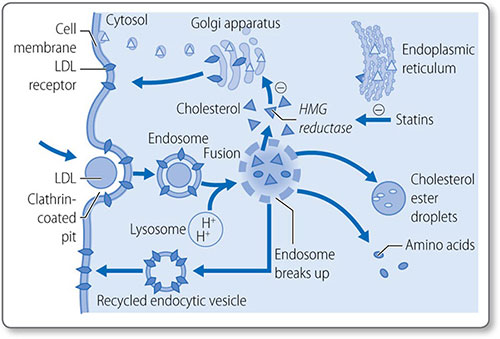

Figure 1.46: Biosynthesis of cholesterol. HMG-CoA, 3-hydroxy-3-methylglutaryl CoA. NADPH, nicotinamide adenine dinucleotide phosphate; ATP, adenosine triphosphate.

This process starts with the isomerization of isopentenyl pyrophosphate to form dimethylallyl pyrophosphate.

Formation of squalene epoxide The third stage is the cyclization of squalene to form squalene epoxide. This requires O2 and NADPH. Squalene epoxide then undergoes cyclization to lanosterol in a reaction catalyzed by cyclase. Lanosterol is then converted to cholesterol, a 27-carbon molecule, by the removal of three methyl groups and the reduction of a double bond by NADPH.

79Regulation of cholesterol synthesis Cholesterol synthesis is regulated by mechanisms that sense the cellular level of cholesterol and modify HMG CoA reductase levels and activity:

- Sterol regulatory element: a transcription factor that inhibits enzyme gene expression in the presence of sterols

- Non-sterol metabolites: derivatives of mevalonate inhibit enzyme gene expression

- AMP-activated protein kinase: phosphorylates and decreases enzyme activity when ATP levels are low

- Enzyme degradation is also tightly regulated.

Cholesterol absorption

Cholesterol esters in the gut are hydrolyzed by cholesterol esterases, secreted by the pancreas and small intestine, to free cholesterol. Cholesterol must be emulsified to be absorbed: conjugated bile acids form micelles with free cholesterol, fatty acids, monoglycerides, and phospholipids.

Most cholesterol is absorbed in the middle jejunum and terminal ileum through the transmembrane transporter protein Niemann–Pick C1-like 1 protein. 30–60% of dietary cholesterol is absorbed daily. Once absorbed into the intestinal mucosa cell, it is packaged into large lipoproteins called chylomicrons.

Cholesterol esterification

As free cholesterol is cytotoxic, it is esterified in the liver to cholesterol ester by acyl cholesterol acyl transferase. Cholesterol esters are stored in intracellular lipid drops and constitute 70% of plasma cholesterol.

Esterification requires energy-dependent activation of a fatty acid with CoA to form an acyl CoA. The acyl CoA reacts with a hydroxyl group on cholesterol to form an ester.

80Lipoprotein esterification Esterification also occurs in the blood, in lipoproteins, the lipid transport vesicles. This is catalyzed by lecithin-cholesterol acyl transferase and does not require CoA; instead a fatty acid is transferred from lecithin. The enzyme is activated by apolipoprotein A-I, the major apolipoprotein in high density lipoprotein (HDL). Cholesterol esters are in the hydrophobic core of the lipoprotein molecule (Table 1.21).

Lipid absorption and transport: lipoproteins

Lipoproteins are spherical particles with non-polar neutral lipids in their core (i.e. triglycerides and cholesterol esters) and more polar amphipathic lipids (i.e. phospholipids and cholesterol) on their surface (Figure 1.47). They also have apolipoproteins on their surface, which bind lipids, cell receptors and act as co-factors for enzymes of lipid metabolism (Table 1.22).

Types

Lipoproteins are classified by their physiochemical properties (Tables 1.21 and 1.23). Generally, larger lipoproteins contain more core lipids, triglycerides and cholesterol esters, and less protein.

Pathways

Lipoprotein metabolism has four main pathways with discrete functions in lipid transport.

|

- The exogenous pathway

- The endogenous pathway

- Intracellular cholesterol transport

- Reverse cholesterol transport.

The exogenous pathway

The exogenous lipoprotein pathway transports lipids absorbed by the intestine to the liver and peripheral cells (Figure 1.48).

- Chylomicrons are assembled in the endoplasmic reticulum of endocytes by combining triglycerides with apolipoprotein B-48

- They are secreted into the circulation, where they acquire additional lipoproteins (e.g. apolipoproteins E and CIIII) from HDL

- Apolipoprotein C-II activates lipoprotein lipase on the luminal surface of endothelial cells, which hydrolyzes chylomicrons to free fatty acids

- The free fatty acids are either taken up by adipose tissue and stored as triglycerides or taken up by muscle and used as an energy source.

|

Remnant particles Chylomicrons are progressively hydrolyzed to chylomicron remnant particles. The surplus phospholipids and apolipoprotein A-I, are transferred back to HDL. Remnant particles are taken up by the liver through via hepatic apolipoprotein E and B-48 receptors. The triglycerides returned to the liver are used to power the biosynthetic activity of the liver, or they are repackaged with apolipoprotein B100 and secreted as very-low-density lipoprotein (VLDL) particles.

The endogenous pathway

This pathway transfers triglycerides synthesized by/transferred to the liver to peripheral cells for energy metabolism (Figure 1.49).

|

Figure 1.48: The exogenous lipoprotein pathway. apo, apolipoproteins; CE, cholesteryl ester; CETP; cholesteryl ester transfer protein; CHOL; cholesterol; CM, chylomicrons; FFA, free fatty acids; HDL, high-density lipoprotein; IDL, intermediate-density lipoprotein; TG, triglycerides; VLDL, very-low-density lipoprotein.

Lipoproteins in the endogenous pathway contain apolipoprotein B-100, particularly VLDLs, which also contain apolipoprotein E and apolipoprotein C. The apolipoprotein C-II on the surface of VLDLs activates lipoprotein lipase on the surface of endothelial cells, which hydrolyze triglycerides to glycerol and fatty acids. The progressive hydrolysis of triglycerides in the core of a VLDL particle transforms it into intermediate density lipoprotein and eventually LDL.

About half of the apolipoprotein B100 particles in the exogenous pathway are removed by hepatic remnant receptors before undergoing complete hydrolysis. The remaining portion is converted to LDL. The triglyceride in LDL is further depleted by the cholesteryl-ester transfer protein, a plasma enzyme that removes triglycerides from LDL in exchange for cholesterol esters from HDL. During the transformation from VLDL to LDL, excess surface phospholipid and lipoproteins (except apolipoprotein B-100) are transferred to HDL.

Figure 1.49: The endogenous lipoprotein pathway. apo, apolipoproteins; CE, cholesteryl ester; CETP; cholesteryl ester transfer protein; CHOL; cholesterol; CM, chylomicrons; FFA, free fatty acids; HDL, highdensity lipoprotein; IDL, intermediate-density lipoprotein; LDL, low-density lipoprotein; TG, triglycerides; VLDL, very-low-density lipoprotein.